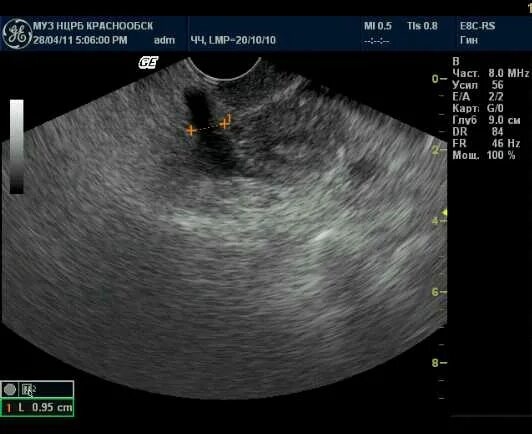

Позадиматочное пространство